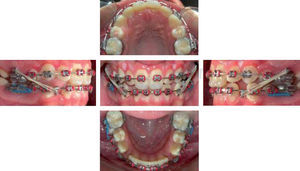

PROGRESIÓN DEL TRATAMIENTOSe inició el tratamiento con las extracciones de los cuatro primeros premolares, posteriormente se colocó el arco lingual y se cementó la aparatología convencional slot 0.22” para ejecutar la técnica MBT (brackets) para iniciar con la fase de alineación y nivelación dental.

Sólo los arcos inferiores fueron cinchados (doblez del arco distal a los tubos de los molares) para evitar la inclinación de los incisivos y los superiores dejados libres procurando proinclinación durante todo el tratamiento.

Luego de dos meses se emplearon resortes de coil abierto entre laterales y premolares superiores para mantener el espacio de los caninos retenidos e iniciamos la retracción canina inferior con cadenas elásticas (CE) sobre arcos de 0.018” de acero inoxidable (AI) (Figura 3).

Ocho meses más tarde, se retiró el arco lingual y se colocó arcos rectangulares 0.019 x 0.025” inferior de nitinol para nivelar y arco 0.014” de nitinol superior para incluir los caninos superiores en la arcada (Figura 4).